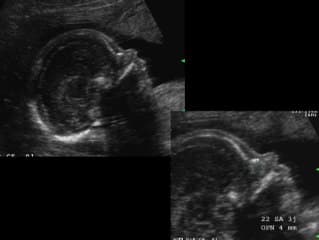

Vous y trouverez des conférences présentées lors des congrès nationaux et internationaux, des cours magistraux dispensés par des experts reconnus, des démonstrations pratiques sur des cas cliniques réels, ainsi que des podcasts et tables rondes sur les dernières avancées de la spécialité.